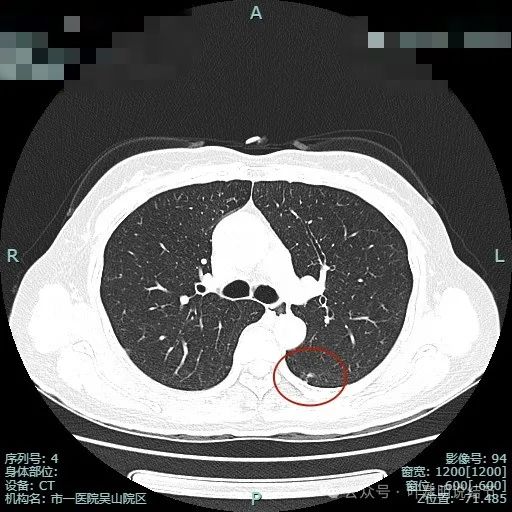

出现小空泡征以及偏实性成分,并有淡磨玻璃成分,整体轮廓较清,瘤肺边界较为清楚。

叶间胸膜有牵拉,病灶内部密度欠均匀。表面有浅分叶征。